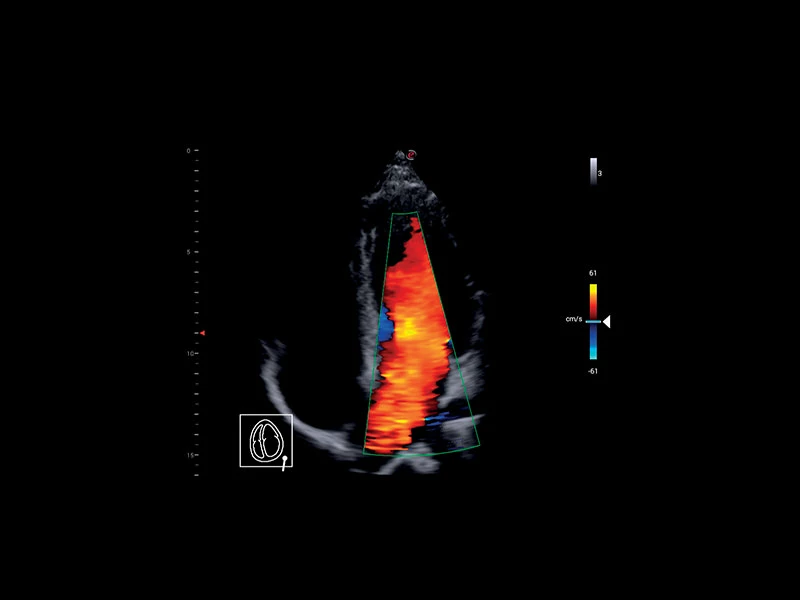

MyLab™9 Platform - Ultra-sensitivity Colour Doppler for precise visualization pulmonary veins

MyLab™9 Platform - Ultra-sensitivity Colour Doppler for precise visualization pulmonary veins